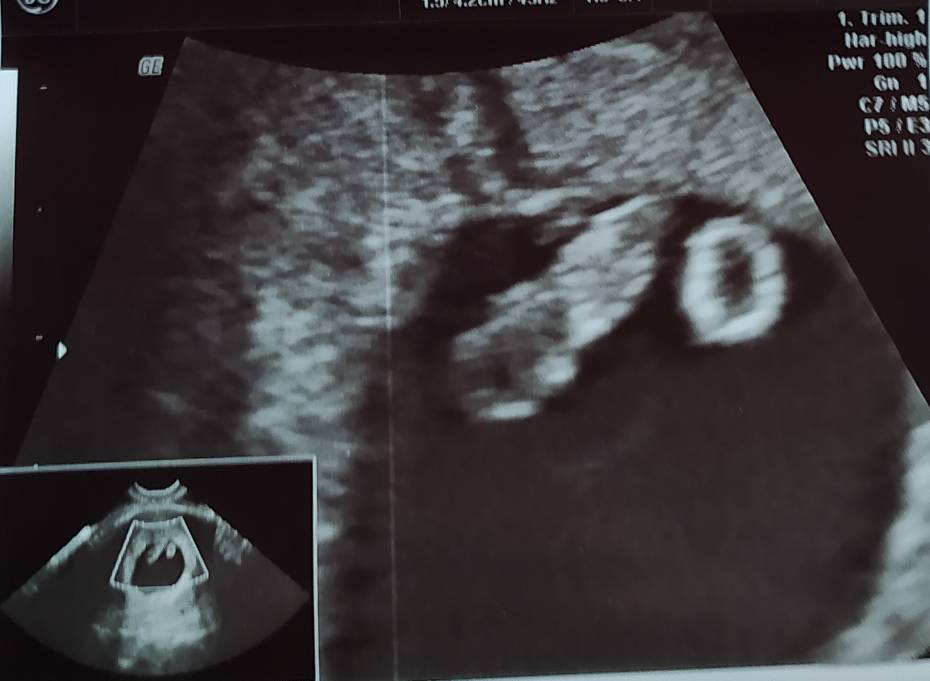

Ja dziś po wizycie, termin się utrzymał, więc dziś jest 9+1, Skrzacik rośnie i ma całe 2,5 cm. 😃 Następna wizyta za 2 tygodnie i będziemy omawiać kiedy prenatalne. ☺️

Termin mam na 31.01, a lekarz dalej twierdzi, że owu była przesunięta. Według OM 8t2d według USG 7t3d.

Moje USG to dopiero fasolka w porównaniu z Waszymi maluszkami.

Moje USG to dopiero fasolka w porównaniu z Waszymi maluszkami. Zobacz załącznik 1286695